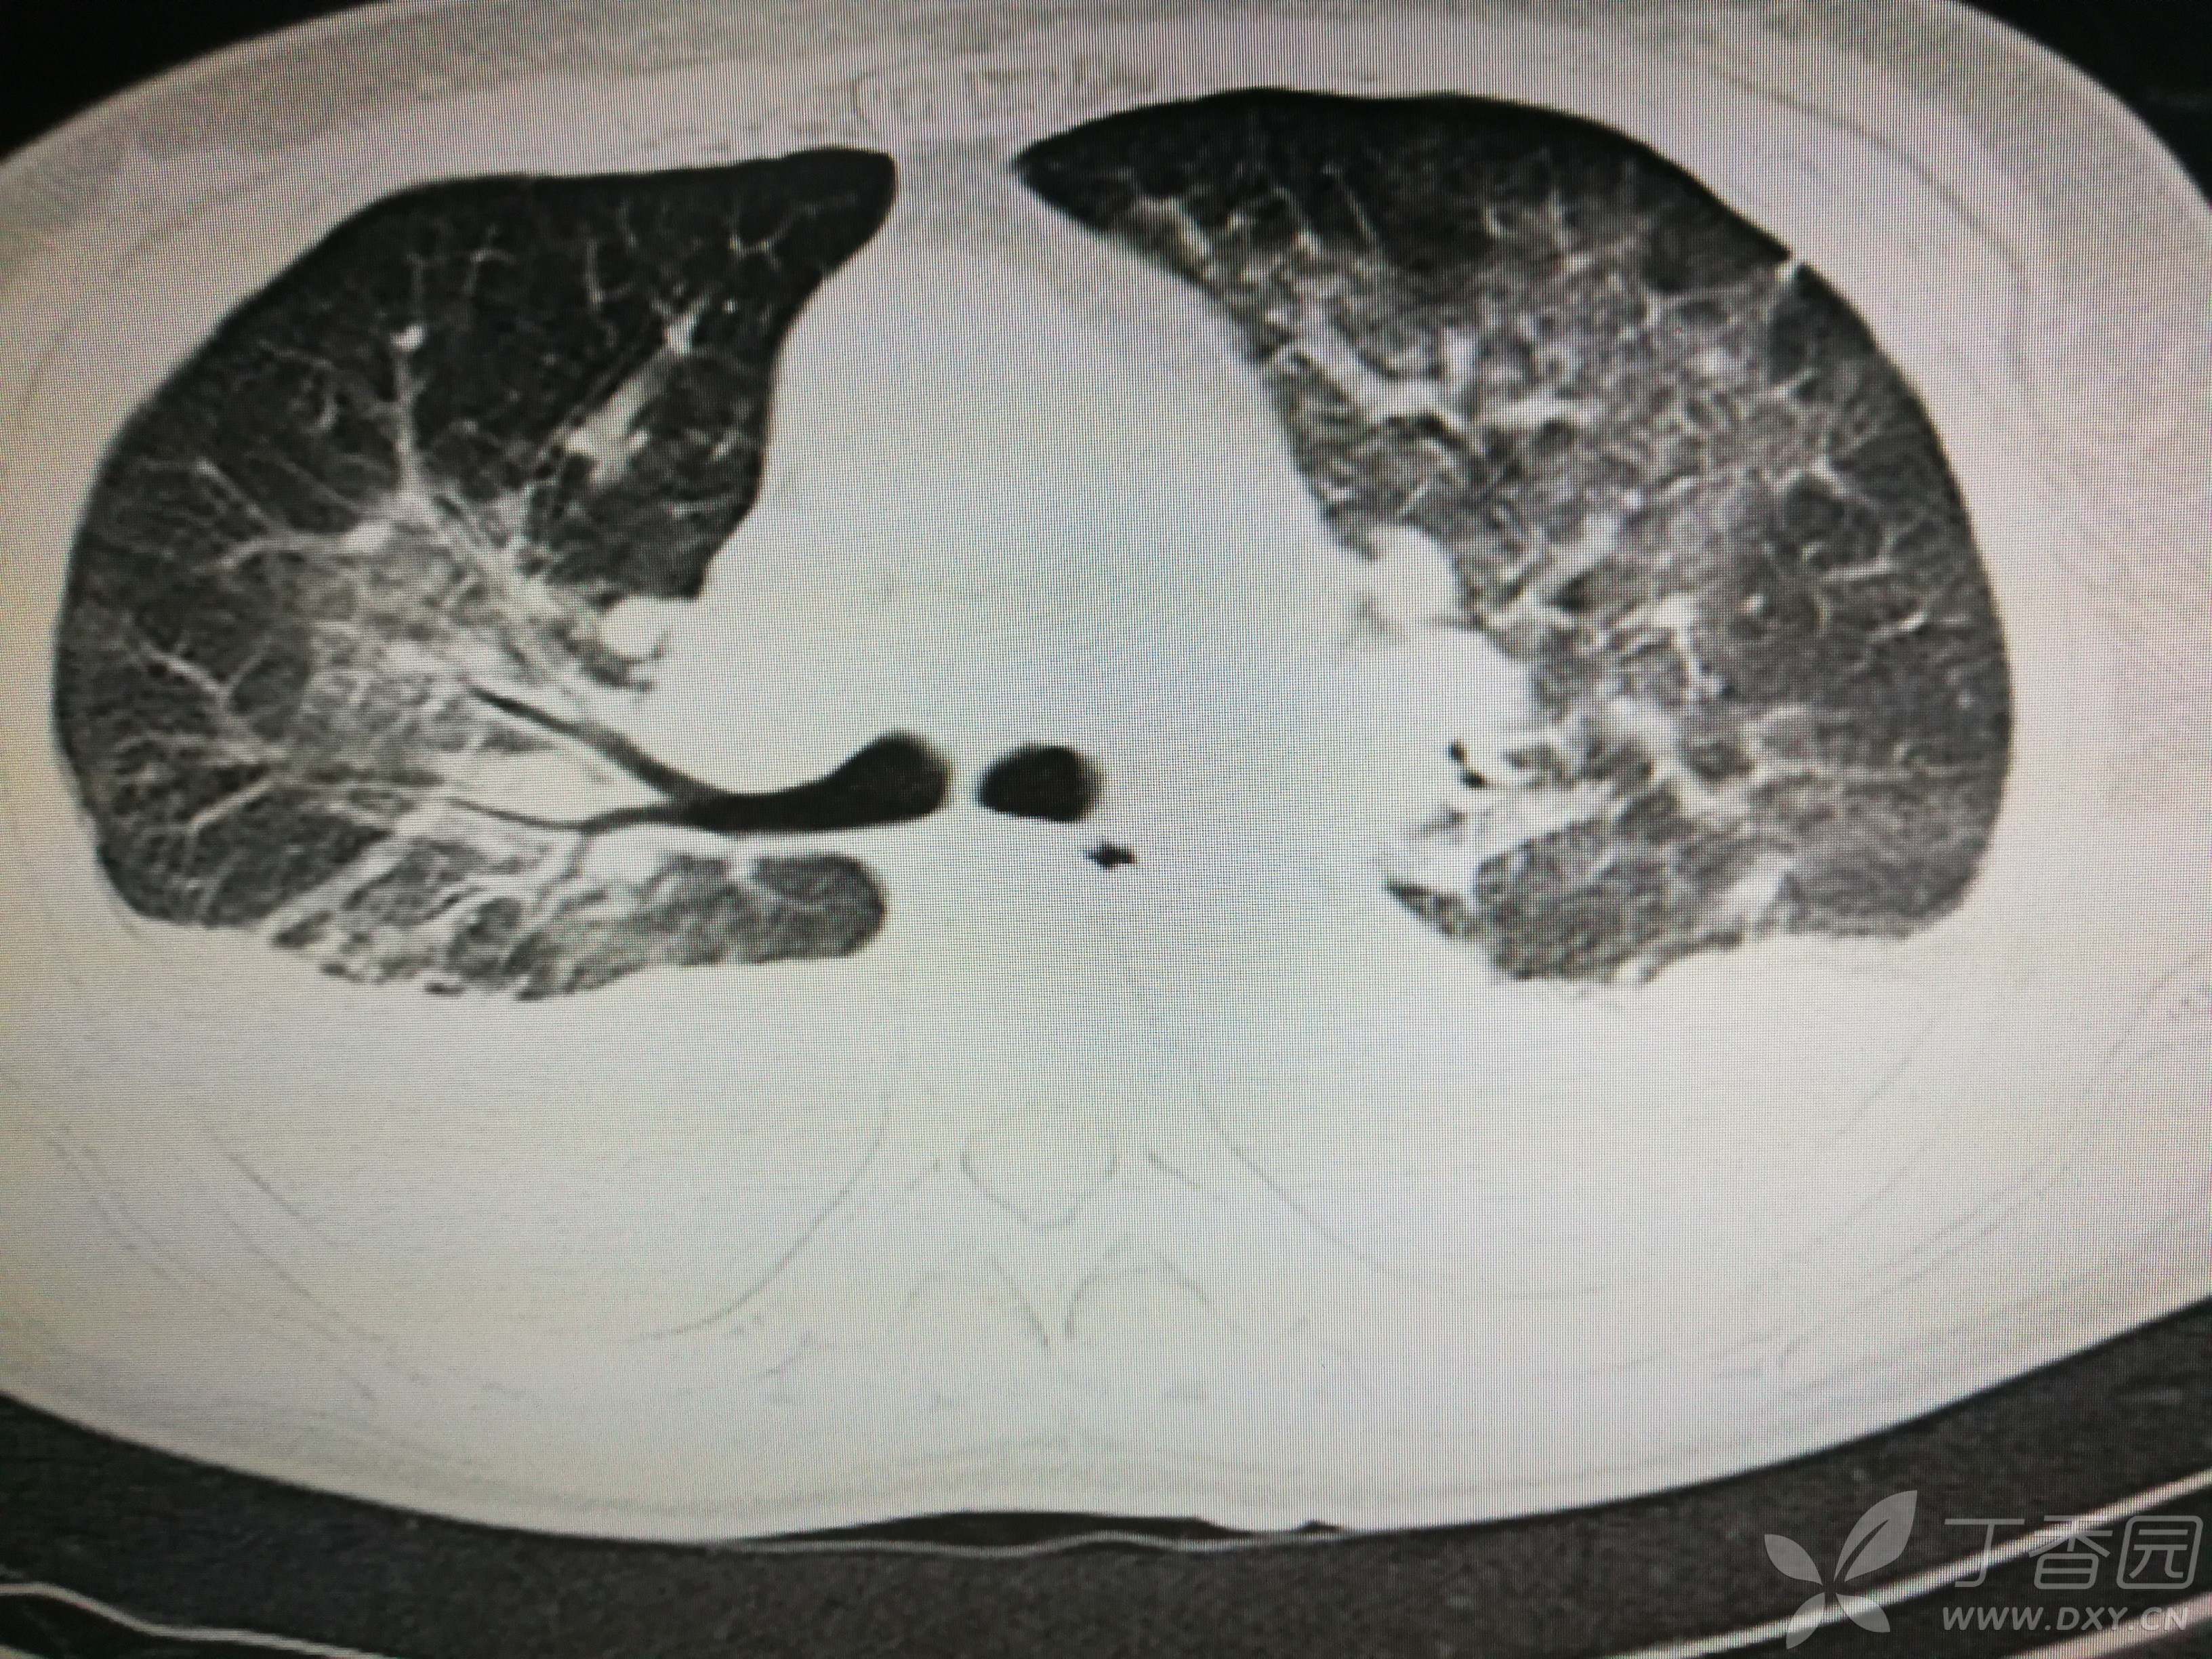

给予低分子肝素钙针抗凝、七叶皂苷钠针消肿及骨牵引固定等等治疗。入院后第四天行“左侧股骨下段骨折切开复位内固定术”(术前查双下肢彩超:双下肢深静脉血流通畅),手术顺利,术后予预防感染、预防血栓形成等治疗。术后患者无明显发热,生命体征平稳。术后第四天复查血常规:白细胞13.4×109/L,血红蛋白84g/L,血小板在正常范围。生化:白蛋白35.7g/L,余无明显异常。当天,患者开始出现轻度胸闷气急,可耐受。术后第五天患者胸闷气急加重,无胸痛,无背痛,无咯血,无意识障碍,无头晕头痛,无恶心呕吐等,急查凝血功能:纤维蛋白原降解产物12mg/L,D二聚体4000ug/L,余无明显异常。查动脉血气分析:pH7.52,氧分压62mmHg,二氧化碳分压30mmHg,碱剩余1.8mmol/L,乳酸1.0mm/L,血红蛋白86g/L。查胸部CT见下(先视频后图片):